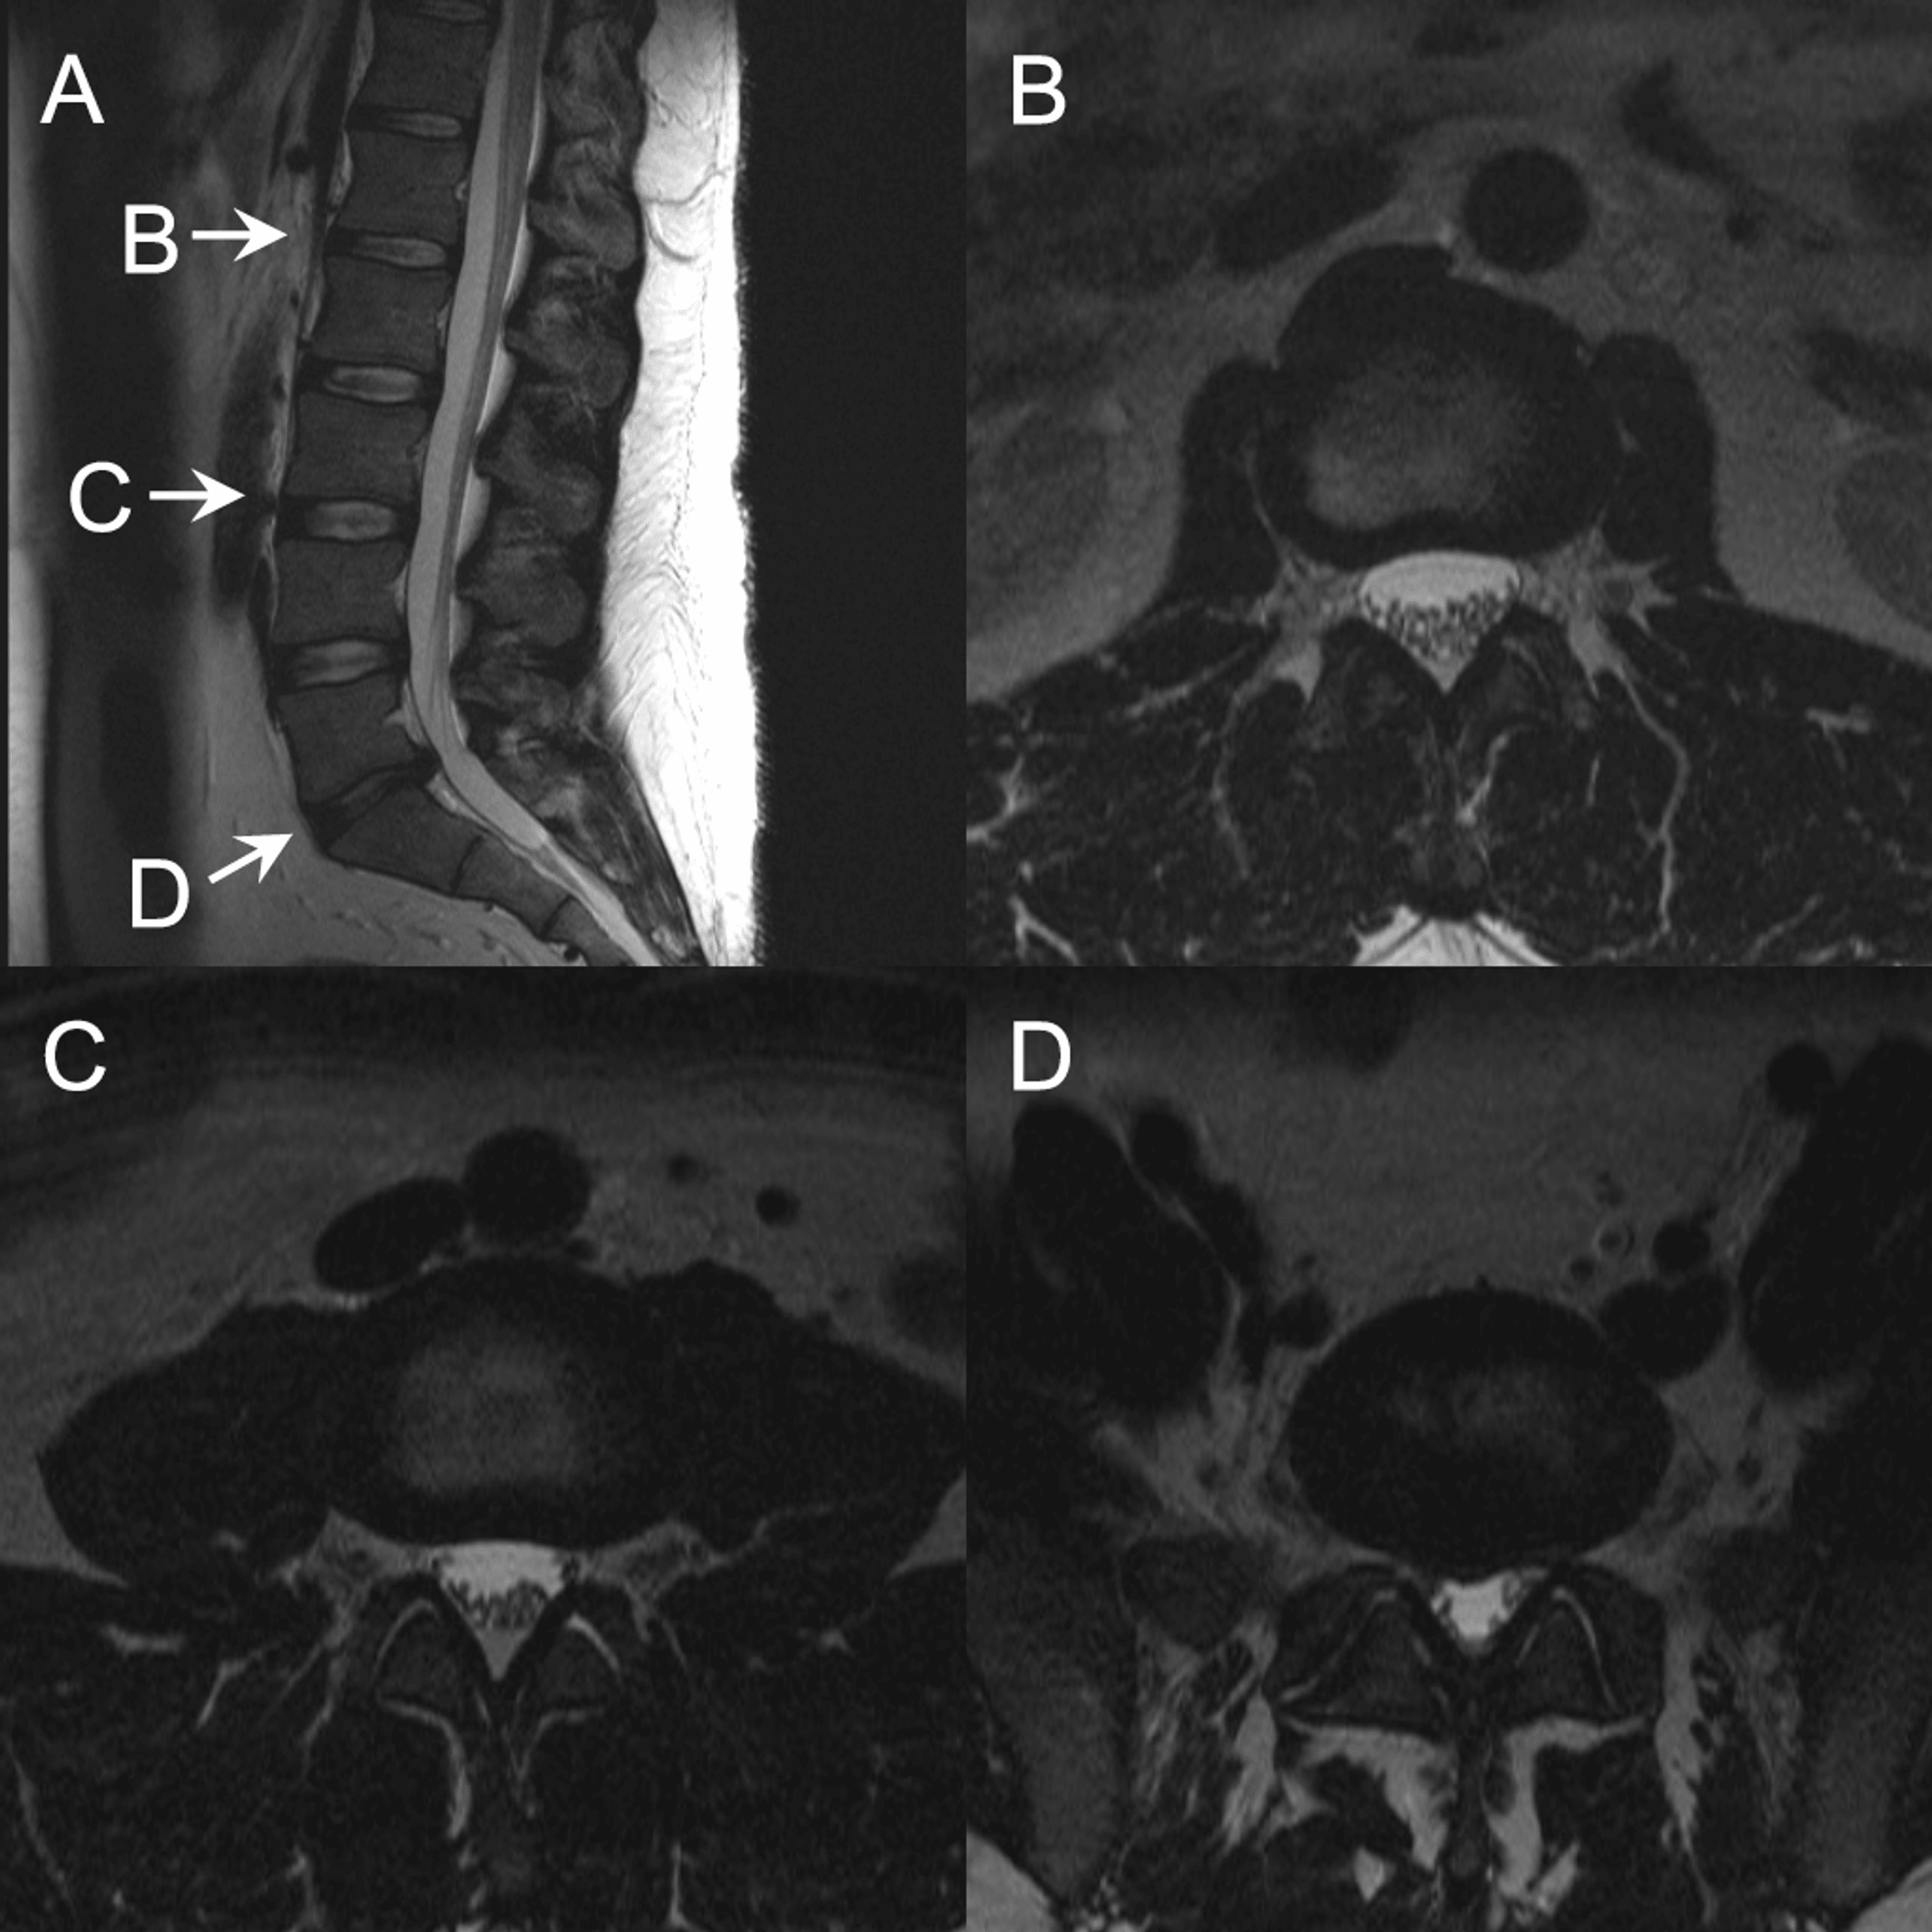

Coronal section through the third and fourth lumbar vertebrae Intervertebral Disk Space Narrowing Intervertebral disc disease is a common condition characterized by the breakdown (degeneration) of one or more of the discs that separate the bones of the spine (vertebrae), causing pain in the. When symptoms do occur, they typically include pain and stiffness in the neck. Most people experience no symptoms. In the early stage of ddd, the intervertebral discs lose their. Intervertebral Disk Space Narrowing.

From radiologykey.com